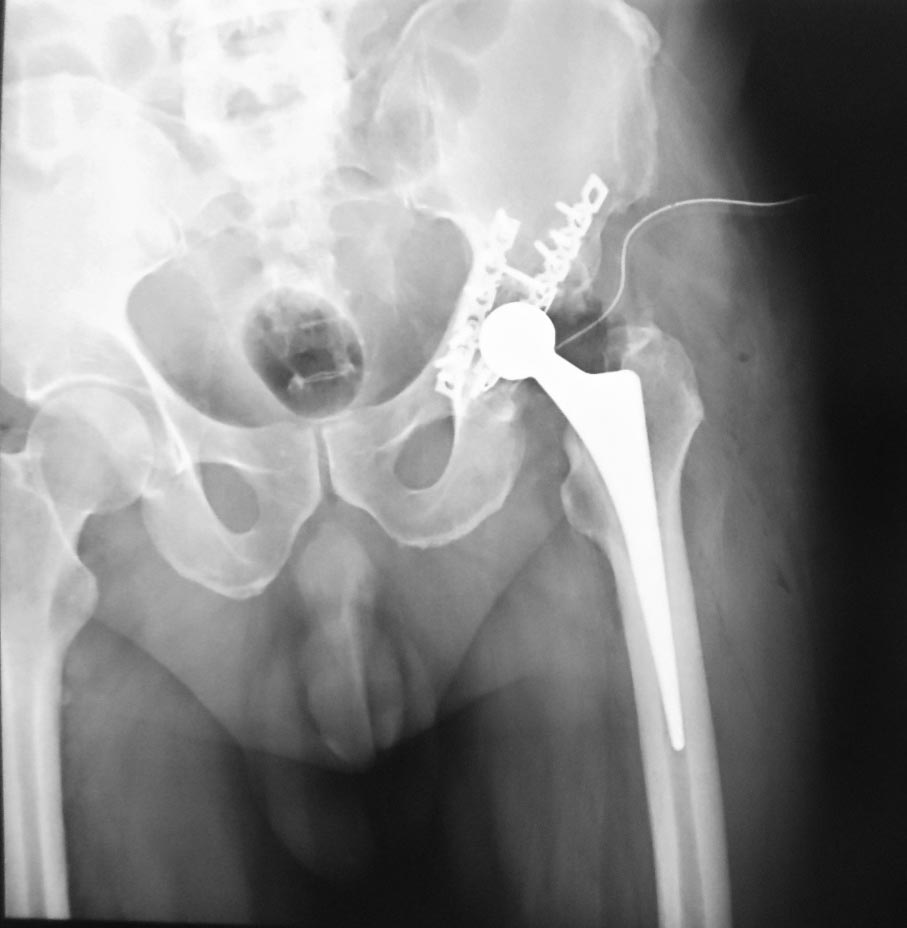

Как и обещал, снимки после эндопротезирования.

Установили комбинированный протез: цементную чашку, безцементную ножку Spotorno.

Сохраняется небольшое укорочение конечности не более 1 см.